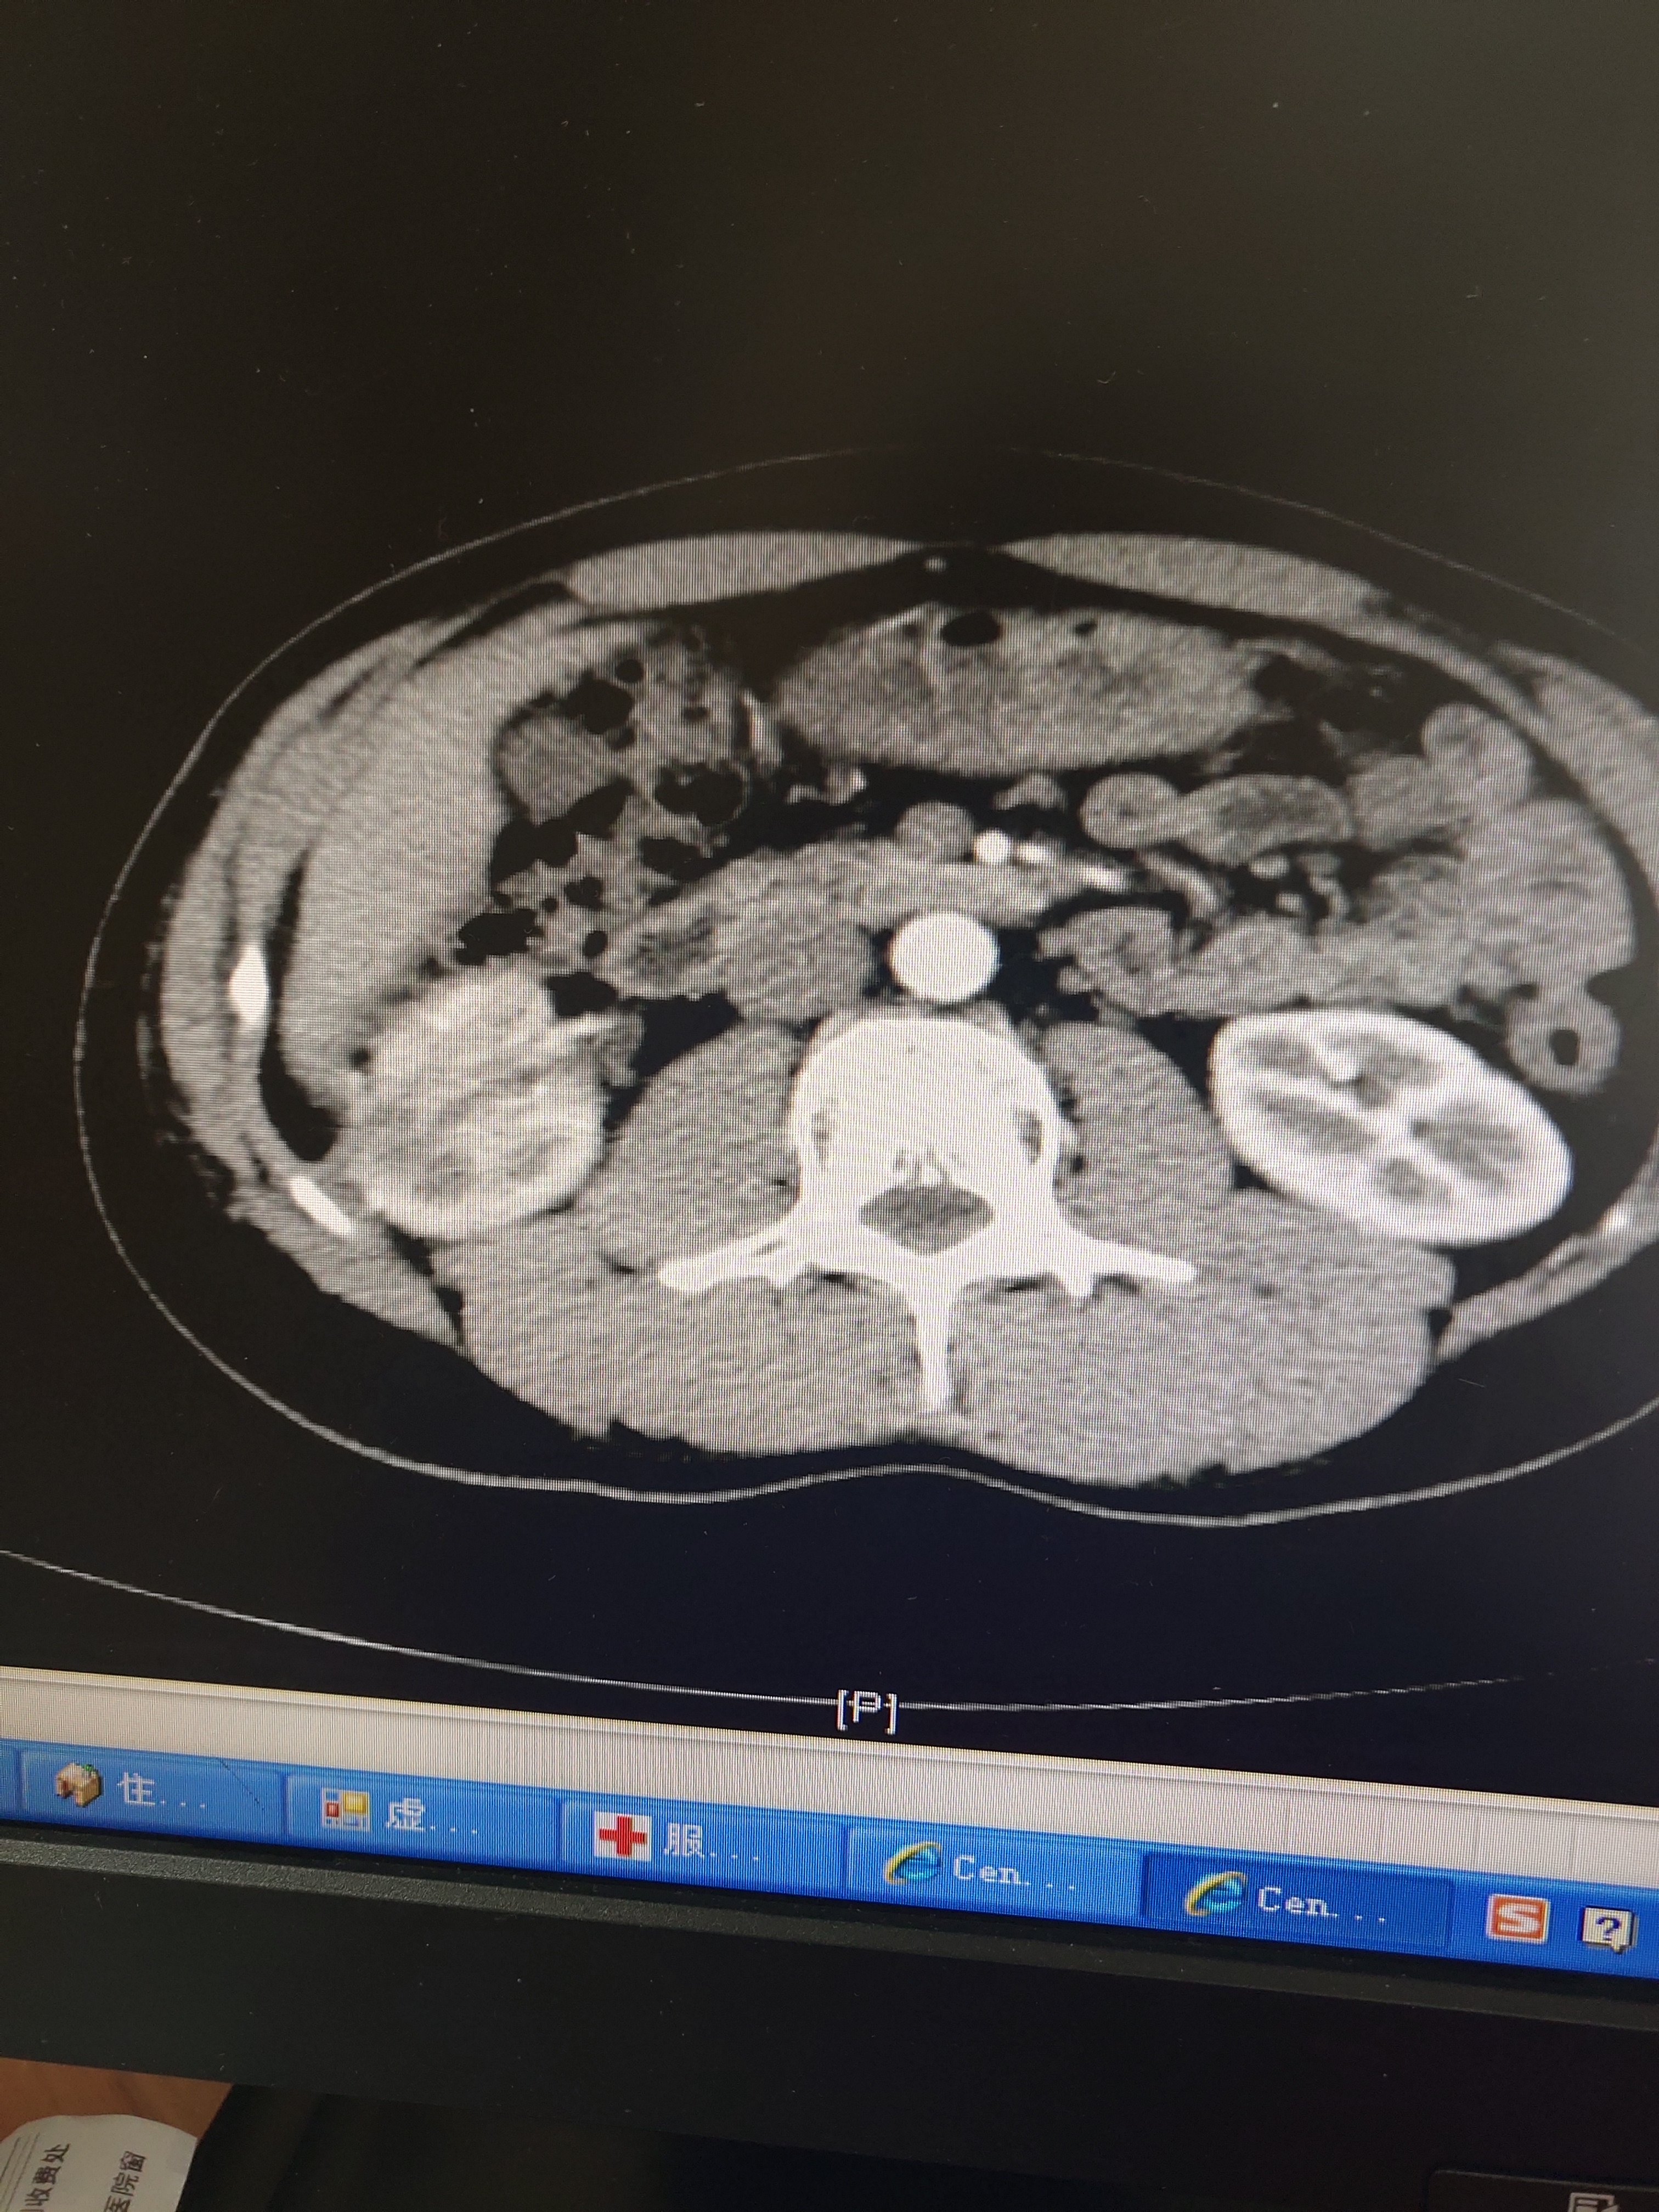

右肾肿瘤,发现7年